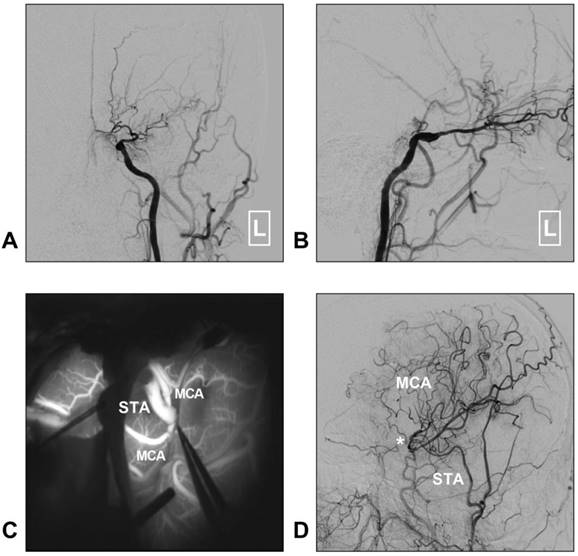

Figure 3

STA-MCA bypass for MMD. A-B: Left CCA angiogram shows steno-occlusive alteration of the ICA terminal; the ophthalmic artery is preserved. C: Intraoperative indocyanine green angiography shows that an STA-MCA bypass is established. D: Follow-up DSA shows that the distal MCA is reconstructed. The asterisk indicates the anastomosis point. Abbreviations: CCA: common carotid artery; DSA: digital subtraction angiography; MCA: middle cerebral artery; MMD: moyamoya disease; STA: superficial temporal artery.

Although STA-MCA bypass has been described as a low-flow system, it is sufficient for MMD [35]. Moreover, chronic dilatation of the STA has occasionally been observed after bypass surgery performed in MMD with the aim of providing more blood flow [40]. A typical case of MMD treated with STA-MCA bypass is described in Figure 3.